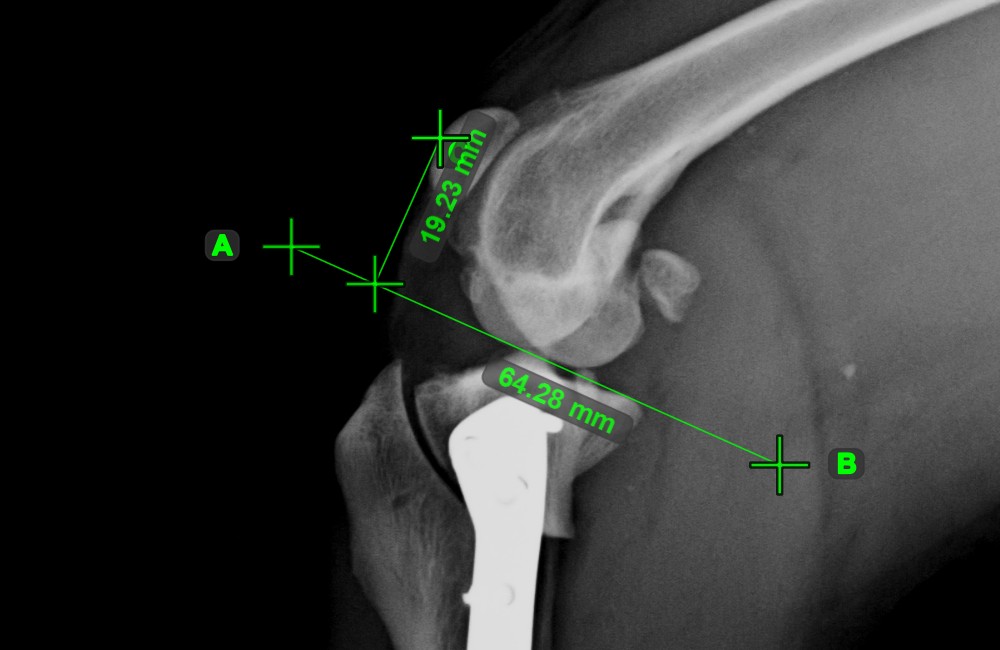

Line Measurement¶

Select the Line Measurement tool and assign it to one of the available mouse buttons. Place the start and end points on the scene or select them from already existing points on the image. The distance between the two points will be automatically

calculated by using the default calibration data, or the recalibrated data by the length calibration measurement.

Modify the start and end point by using the Select/Move Item tool. The distance between the two points will be automatically recalculated.